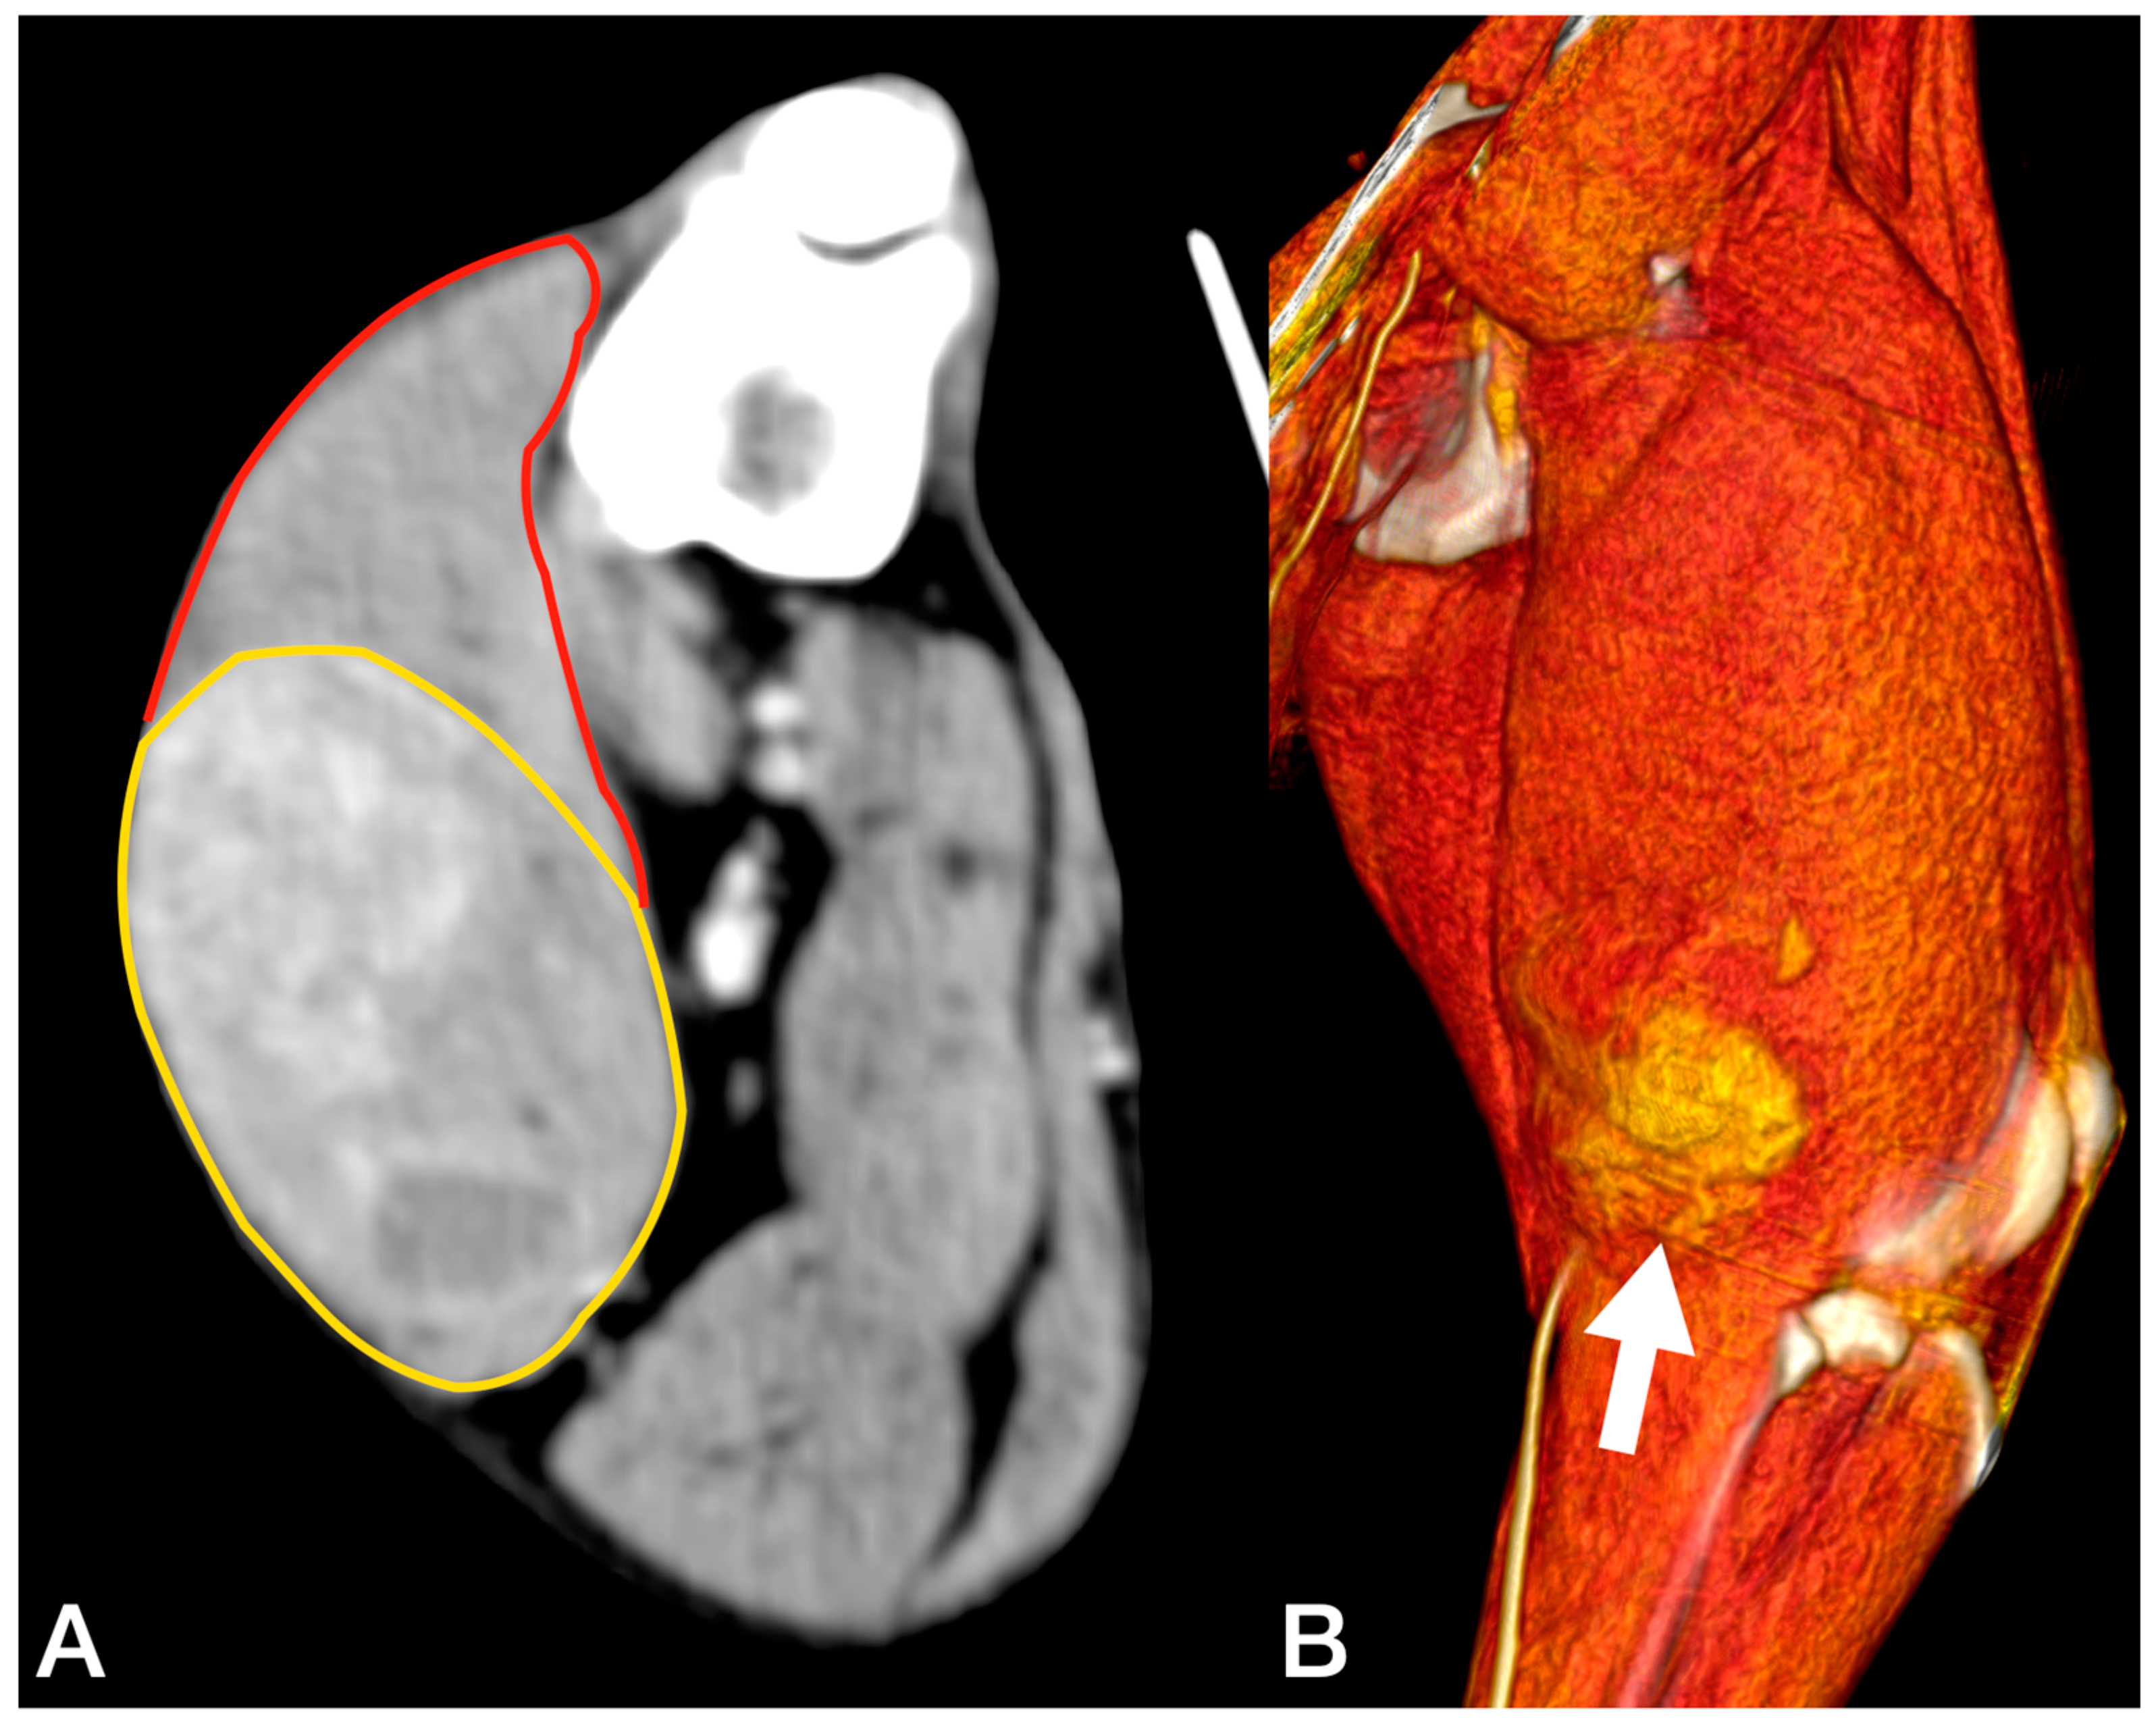

The dog was positioned in left lateral recumbency, and an elliptical skin incision was performed with 3 cm margins around the biopsy site on the lateral surface of the thigh. The incision was then extended proximally to the ischiatic tuberosity and distally to the tibial crest. The subcutaneous fat and the superficial fascia were incised under the skin incision. After dissecting the fascia lata, the biceps muscle was isolated from the vastus lateralis muscle. The craniodistal insertion of the biceps was isolated and resected from the craniolateral aspect of the tibial crest. Finally, the biceps muscle was freed from the mid-proximal femur, dissecting the fibres adherent to the bone (Figure 3A).

Figure 3.

(A) Intra-operative picture of the detachment of the biceps from distal to proximal. (B) Medial aspect of the anatomic sample, the tumour is confined within the fascial layer, marked with white arrow.

3.3. Case 3

An 8-year-old 35 kg spayed female mixed breed was referred for a 10 cm mass localised between the dorsal neck and the left scapular region, which had been noted a week earlier and had grown rapidly. At clinical examination, the mass appeared as a painful, firm, subcutaneous lesion adhering to the underlying tissues. No regional lymphadenopathy was detected. The cytology performed by the referring veterinarian was indicative of a malignant mesenchymal sarcoma. Total body CT confirmed the anatomic confinement of the tumour to the dorsal surface of the splenius capitis (Figure 5). No other anomalies were found based on the CT exam.

Figure 5.

Tomographic appearance of the neoplasm within the splenius capitis muscle between the seventh cervical vertebra and the medial surface of the scapula. The yellow line delimitates the tumours, and the red line is the splenius capitis muscle.